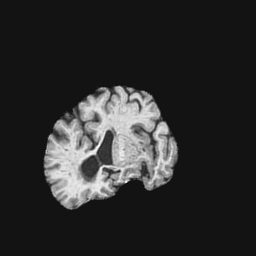

Exp. 2: Fetal brain data is used to test the robustness of our approach under real conditions. Fetuses younger than 30 weeks very often move a lot during examination. Fast MRI sequences allow artifact free acquisition of individual slices but motion between slices corrupts consistent 3D information. Fig. 3 shows that our method is able to accurately predict Ti^^subscript𝑇𝑖\hat{T_{i}} also under these conditions. For this experiment we use ωisubscript𝜔𝑖{\omega_{i}} from three orthogonally overlapping stacks of ssFSE slices covering the fetal brain with approximately 20-30 slices each. We are ignoring the stack transformations relative to the scanner and treat each ωisubscript𝜔𝑖{\omega_{i}} individually. For ΩtrainsubscriptΩ𝑡𝑟𝑎𝑖𝑛\Omega_{train}, 28 clinically approved motion compensated brain reconstructions are resampled into a 150×150×150150150150150\times 150\times 150 volume with 1mm×1mm×1mm1𝑚𝑚1𝑚𝑚1𝑚𝑚1mm\times 1mm\times 1mm spacing. A density of 500 unique sampling normals has been chosen via the Fibonacci sphere sampling method with 25 sampling planes evenly spaced between -25 to +25 on the Z-axis. This gives a plane spacing of 2mm, sampling only the middle portion of the fetal brain. Training took approximately 10hrs for 30 epochs. Prediction, i.e., the forward pass through the network, takes approx. 12 ms/slice.

Figure 3: Comparison of a single slice from a heavily motion corrupted stack of ssFSE T2 weighted fetal brain MRI (a); axial multi planar reconstruction of one sagittal input stack (b); a slice at approximately the same position through a randomly selected training volume (c); failed reconstruction attempt using standard SVR based on three orthogonal stacks of 2D slices (d) (the fetus moved heavily between the acquisition of the individual stacks); reconstruction based on SVRNet Ti^^subscript𝑇𝑖\hat{T_{i}} regression (e); SVR initialised with SVRNet transformations after eight iterations of SVR (f). Note that (e) and (f) are reconstructed directly in canonical atlas co-ordinates.